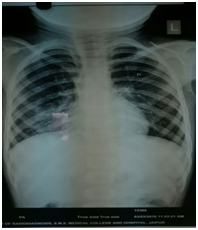

Case 1: An 18 girl aged 18 gave a history of 13 years of cough, which had recently become more troublesome with mucopurulent sputum. She had been attending a rural health center for the cough for several years. Radiographs were normal initially. Subs X Rays showed obstructive emphysema on the left side. She remembered swallowing a whistle when she was much younger (around 5 years of age). Before the diagnostic bronchoscopy, a computed tomography (CT) was performed that revealed a soft tissue density in the left main bronchus (Figure 1). Rigid bronchoscopy performed a plastic whistle successfully Retrieval was by under general anesthesia. (Figure 2) There was considerable granulation tissue around the FB.

Case 2: A 5 year old girl reported to the hospital with history of chronic cough since 2 years; she had episodes of recurrent URTI. There was no history of FBA. She had been treated many times by physicians for acute bronchitis in this period and experienced temporary relief after medication. She had diminished chest movement on the right and dullness to percussion was elicited on the right as well. She had a markedly diminished breath sound over the right lung field. Chest X ray was advised which showed a radiopaque object lodged in the right main bronchus with resultant atelectasis of the entire left lung and compensatory emphysema of the right lung (Figure 1) Bronchoscopy revealed a black metallic stud in the right main bronchus. a mass of granulation tissue surrounded the body (Figure 3) (Figure 4) (Figure 5).

Radiographic examination is an invaluable asset in the diagnosis of an aspirated foreign body.20–22 In a radioopaque foreign body, examination is straightforward; when the foreign body is nonradiopaque, secondary changes such as atelectasis and obstructive emphysema are of diagnostic importance. The common radiological sign in our series was obstructive emphysema. A CT thorax is not frequently requested but this is indicated if there is high index of suspicion regarding chronic pulmonary changes due to the prolonged presence of FB.23